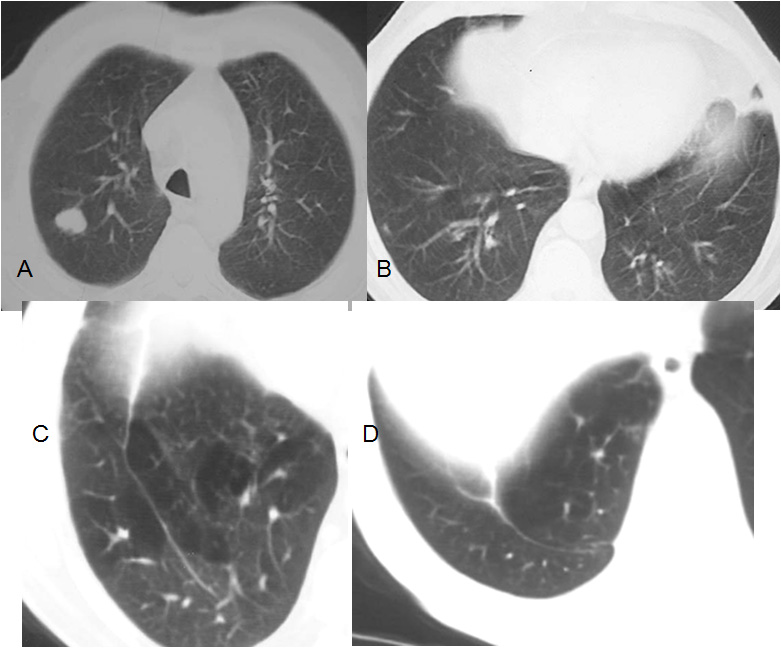

Paciente con nódulo en el lóbulo superior derecho (A). El estudio de TC en el momento del diagnóstico muestra una base pulmonar normal (B). Tras la lobectomía aparece una hiperinfuflación de la base pulmonar (C) alrededor de la cisura accesoria inferior, que es la imagen lineal que atraviesa la base pulmonar de adelante atrás. La última imagen (D) muestra la parte más inferior de la cisura accesoria, con un trayecto en arco que acaba en la pleura.